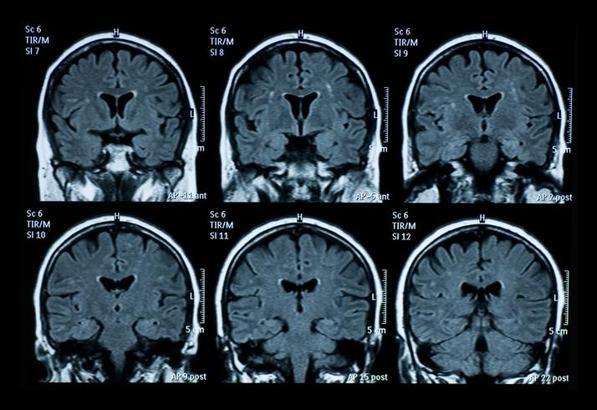

Demans, günlük yaşamı etkileyecek kadar şiddetli hafıza, dil, sorunları çözme ve diğer düşünme becerilerinin kaybını ifade eden genel bir terim. Zamanla sinir hücrelerini tahrip eden ve beyne zarar veren bir dizi hastalığın neden olabileceği bir sendrom.

Genellikle bilişsel işlevlerde, yani düşünceyi işleme yeteneğinde biyolojik yaşlanmanın olağan sonuçlarından beklenenin ötesinde bir bozulmaya yol açıyor. Bilinç etkilenmese de bilişsel işlevlerdeki bozulmaya genellikle ruh hali, duygusal kontrol, davranış veya motivasyon değişiklikleri eşlik ediyor ve bazen de öncesinde görülüyor.